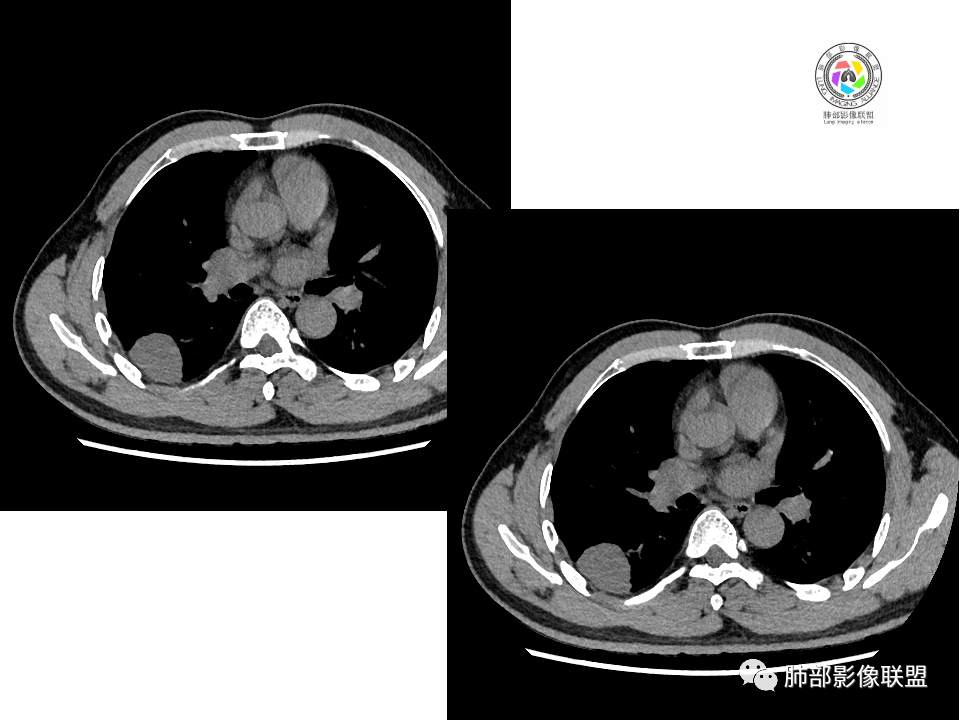

关于结节型隐球菌

1、普通人隐球菌感染的时相:初期的隐球菌感染周围有晕,晕从多变少,或包裹,或吸收,结节实性区可迅速变大。后期(慢性期)的隐球菌周围无明显晕征,边界较清楚。

2、有些模糊晕消失慢的原因:隐球菌对周围肺组织破坏相对不重,周围所供应的营养不多,增殖也不快,呈局部相安无事的状态。隐球菌消灭之后,肺泡间隔的炎症细胞及间质恢复更慢,所以经常能见到隐球菌外面隐约带细丝的模糊影。

3、卫星灶与“蘑菇兄弟”:诊断隐球菌时,建议找卫星灶,卫星灶可以在遥远的地方。可以是遥远地方的微小结节——“小蘑菇兄弟”。有些远处的卫星灶,通常是不规则饱满实性的,晕征不明显。隐球菌的卫星灶非常“隐”,但发现率高达60%多,诊断价值高。

4、卫星灶距离远的原因:隐球菌卫星灶常很远,推测:一次空气来源隐球菌感染进入双肺多处,部分定居繁殖;距离近的隐球菌“蘑菇兄弟”常常是二次感染。

5、周围毛刺纤维、边缘形态等:坏死包裹会使得结节变圆;结节多缺乏明显的分叶征,缺乏局部突出生长能力;如果出现分叶,是由多处肉芽肿中心形成。没有坏死的局限化,结节只是凑合在一起,常呈方形征;毛刺进入晕区(概念源自南边老师),毛刺较短、较软;周围的晕吸收后,会留下不规则边,外面常残留丝状条索;收缩力较弱,临近胸膜对胸膜牵拉不明显。

6、隐球菌的毛刺消失于晕区的解释:隐球菌结节周围有间质淋巴细胞增多,肉芽肿性炎延伸,以及纤维组织增生,形态并不规则,不是因为收缩力。

7、其他:隐球菌实性区相对腺癌更实,一旦实变里面就没空气,胸膜牵拉线(小叶间隔)拉的不太紧。